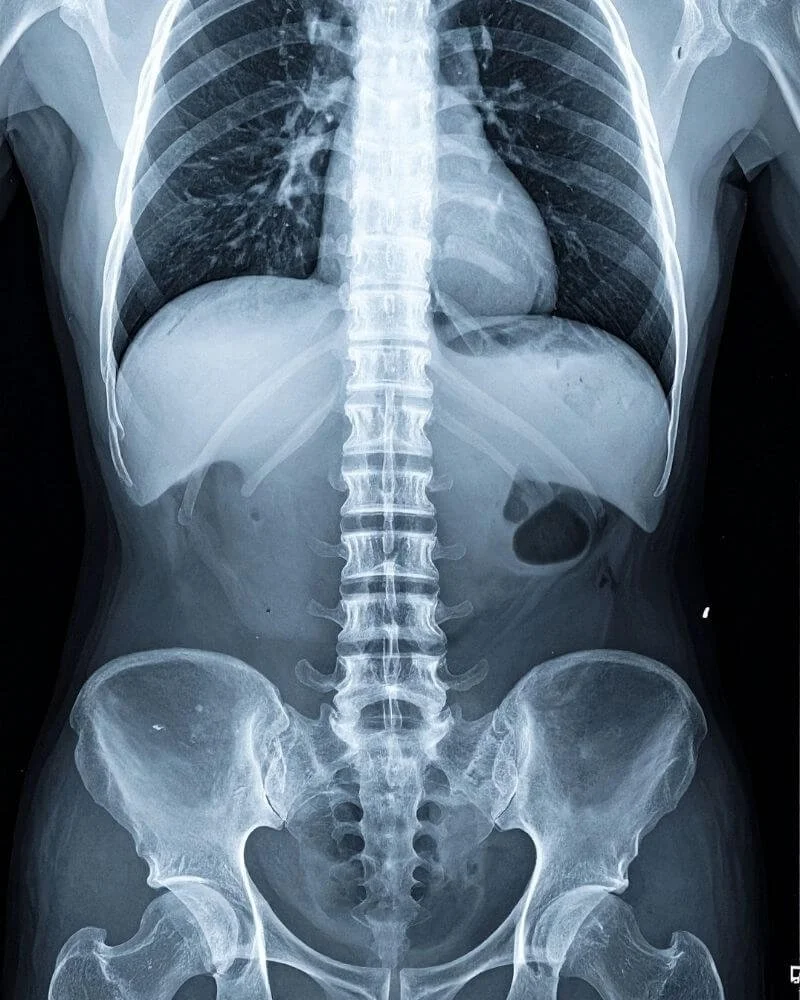

What Is an X-ray and How Does It Help Chiropractors?

An X-ray is a non-invasive imaging technique that uses low levels of radiation to capture detailed images of the internal structures of your body. In chiropractic care, X-rays are primarily used to examine the condition of the spine, bones, and joints. This helps chiropractors accurately diagnose misalignments, injuries, and other spinal issues that may be contributing to your pain or discomfort.

At Renaud Chiropractic Clinic, we use digital X-rays to get clear, high-quality images of your bones, joints, and spine. This allows us to:

• Identify spinal misalignments, which can be a source of pain and discomfort.

• Detect degenerative conditions like arthritis or disc degeneration.

• Identify fractures, stress fractures, or joint abnormalities.

• Examine herniated or bulging discs, which can put pressure on the nerves and cause symptoms like sciatica.

Having a detailed image of your spine and joints helps us diagnose your condition with precision, leading to a more effective treatment plan that targets the root cause of your pain.